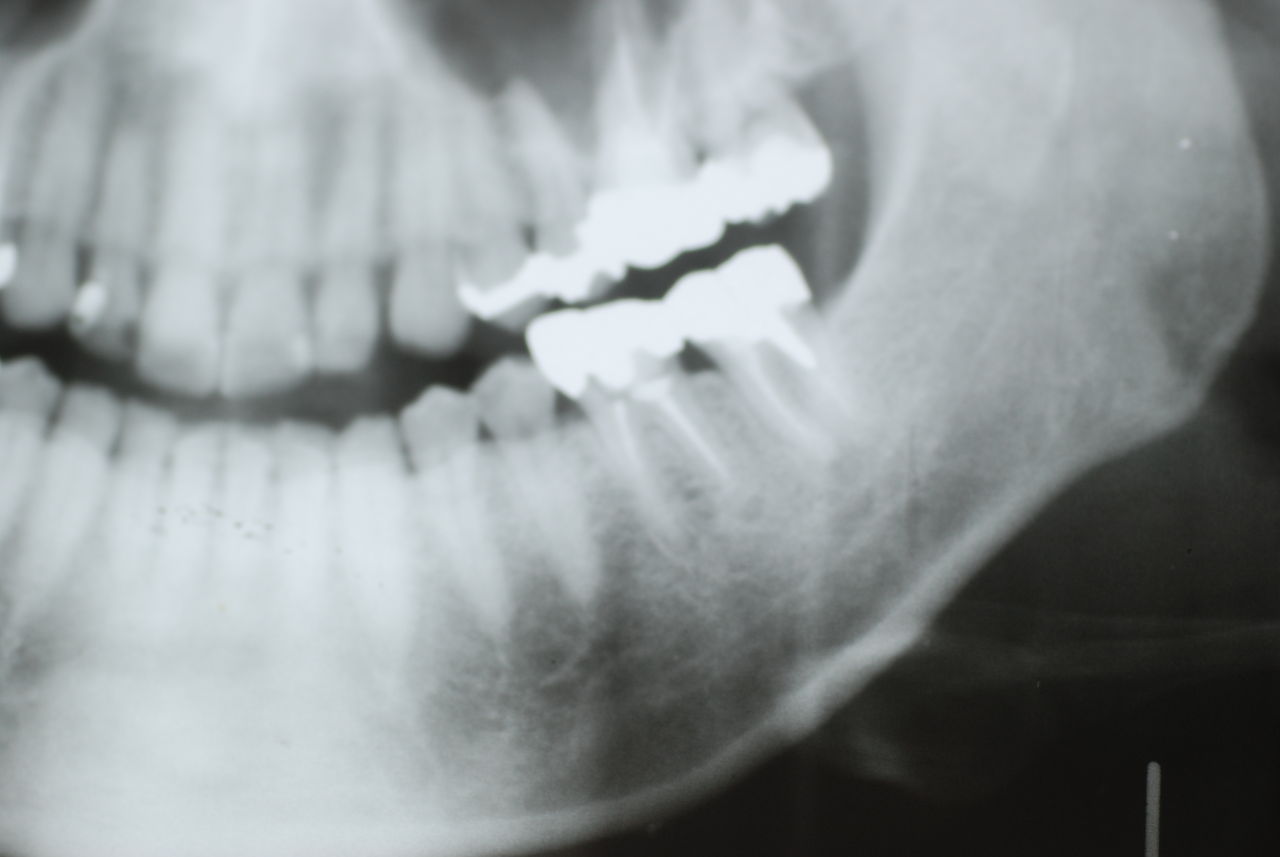

相談しても“問題無い”の説明だけだそうです。調べたところ歯周病は進行しているし、奥歯の大きい歯2本ずつ計4本はしっかり噛んでいないのです。よく噛めないというのはそのことのようでした。これを矯正的に元に戻すことはできない訳ではありませんが、時間と手間がかかるのは間違いないことです。

歯を削らないといいましても結局歯の間を削りスペースを確保したそうですから、何らかの歯に対する傷害はしているのです。それは虫歯や歯周病を起こしやすい理由にもなりますからこれからも要注意なのです。二年間という貴重な時間を費やしていますから患者本人は大変だったと思います。そして二年間を要したならば更に二年間動かないようにするための入れ歯やマウスピースを装着し続けなければいけないのです。